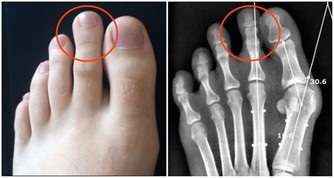

如風濕、關節炎等。另外,芹菜還可以調節體內水分的平衡,改善睡眠。